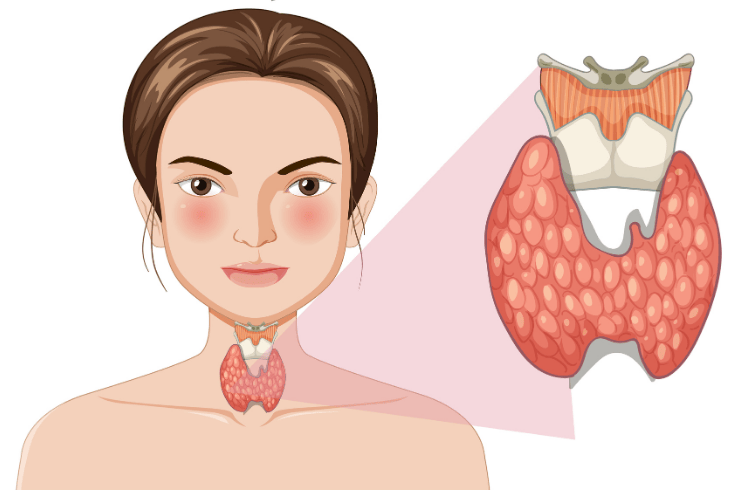

Specialized management of diabetes, thyroid, and hormonal disorders for balanced and long-term health.